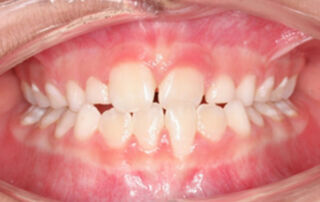

Caso clínico mordida cruzada anterior Pistas Composite – 01

Mordida cruzada anterior tratada con pistas de composite y sin aparatos de ortodoncia. Paciente de 7 años de edad que presenta una mordida cruzada anterior del incisivo central izquierdo superior (2.1) con los incisivos central y lateral izquierdos inferiores (3.1 y 3.2). Ya que presenta una clase I esquelética y [...]